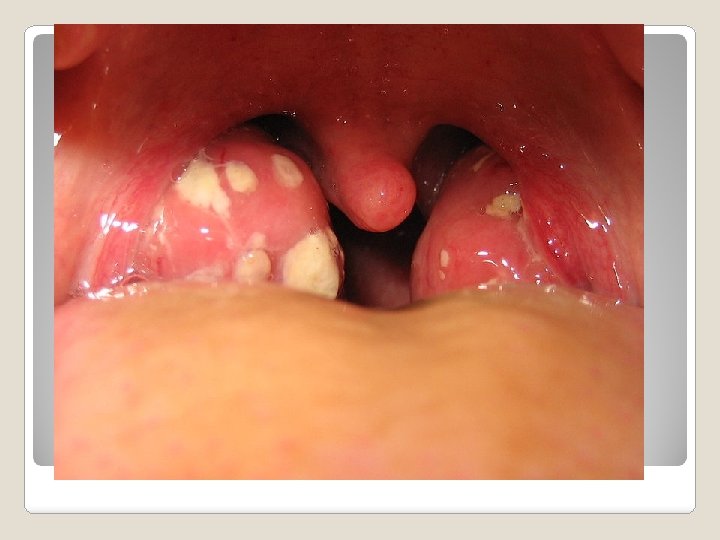

Tonsillitis occurs when the tonsils become swollen and inflamed. The tonsils located in the nasopharynx are often referred to as adenoids. If you suffer from tonsillitis frequently and breathing becomes difficult, they can be removed surgically in a procedure called a tonsillectomy. Tonsillitis